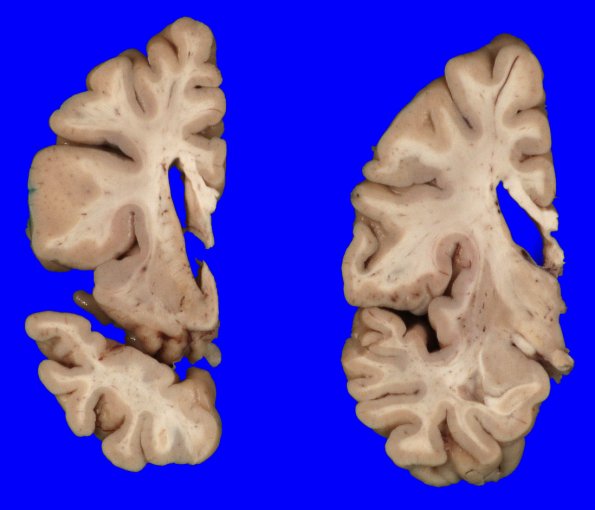

Washington University Experience | NEURODEGENERATION | Huntington Disease | 8B4 Huntington's Dz (Case 8) gross_13

Coronal slicing reveals a moderately dilated lateral ventricle with a small flattened caudate nucleus (3 mm thickness) in fixed specimens.